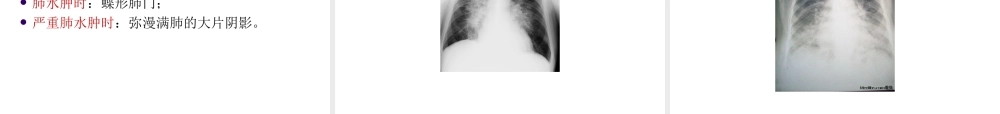

急性心力衰竭临床分类心力衰竭:各种心脏结构或功能性疾病导致心室充盈和(或)射血功能受损,心排血量不能满足机体组织代谢需要,以肺循环和(或)体循环淤血,器官组织血液灌注不足为临床表现的一组综合征。主要表现为呼吸困难、体力受限、和液体潴留。临床分类分类:1.左心衰竭,右心衰竭,全心衰竭。2.急性心衰,慢性心衰。3.收缩性心衰,舒张性心衰。舒张性心衰:又称射血分数正常性心衰(HFPEF),是指心脏射血分数(EF)正常或接近正常(>0.50or0.45),但有心衰症状、体征和临床表现。临床分期心力衰竭分期:1.前心衰阶段2.前临床心衰阶段3.临床心衰阶段4.难治性终末期心衰阶段心力衰竭分级NYHA心功能分级法:I级日常活动量不受限制,不引起呼吸困难乏力II级体力活动轻度受限,一般活动引起心衰症状III级体力活动明显受限,低于平时一般活动引起心衰症状。IV级不能从事任何体力活动,休息状态下也存在心衰症状。运动耐力评价6分钟步行试验轻度心衰>450m中度心衰150-450m重度心衰<150m基本病因1.原发性心肌损害1)缺血性心肌损害:冠心病心肌缺血心肌梗死是引起心衰最常见原因。2)心肌炎和心肌病:病毒性心肌炎原发性扩张性心肌病最常见。3)心肌代谢障碍性疾病:糖尿病心肌病最长见。心肌淀粉样变性,甲状腺功能异常。基本病因2.心脏负荷过重1)压力负荷(后负荷)过重:见于高血压、主动脉瓣狭窄、肺动脉高压、肺动脉瓣狭窄等左右心室心室收缩期射血阻力增加的疾病。2)容量负荷(前负荷)过重:见于心脏瓣膜关闭不全,血液返流,及左右心或动静脉分流性先天性心脏病。伴有全身循环血量增多的疾病。诱因1.感染:呼吸道感染。感染性心内膜炎。2.心律失常:心房颤动是器质性心脏病最常见3.血容量增加:4.过度体力消耗或情绪激动5.治疗不当6.原有心脏病加重或并发其他疾病临床分类急性心衰:指心力衰竭急性发作和(或)加重的一种临床综合征,可表现为急性新发或慢性心衰急性失代偿。临床分类一、急性左心衰竭指急性发作或加重心肌收缩力明显降低、心脏负荷加重,造成急性心排血量骤降、肺循环压力突然升高、周围循环阻力增加,引起肺循环充血而出现急性肺淤血、肺水肿并可伴组织器官灌注不足和心源性休克的临床综合征。临床分类急性左心衰竭慢性心衰急性失代偿急性冠状动脉综合征高血压急症急性心瓣膜功能障碍急性重症心肌炎围生期心肌病严重心律失常临床分类二、急性右心衰竭右心室心肌收缩力急...